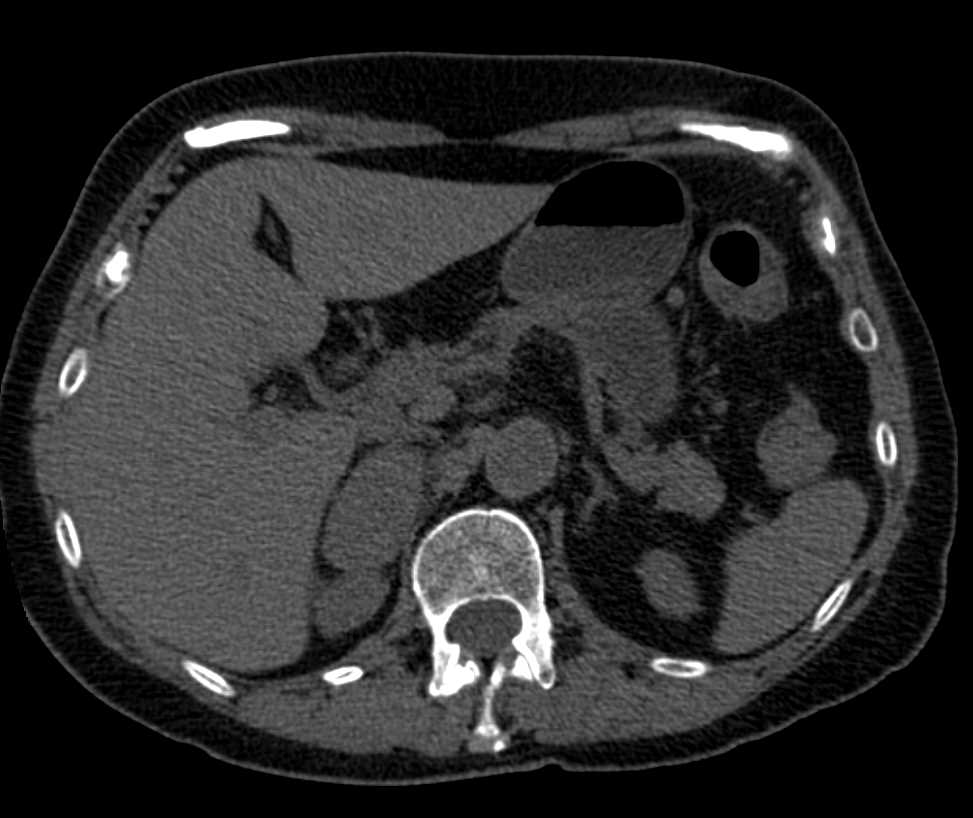

Fat Poor Left Adrenal Adenoma